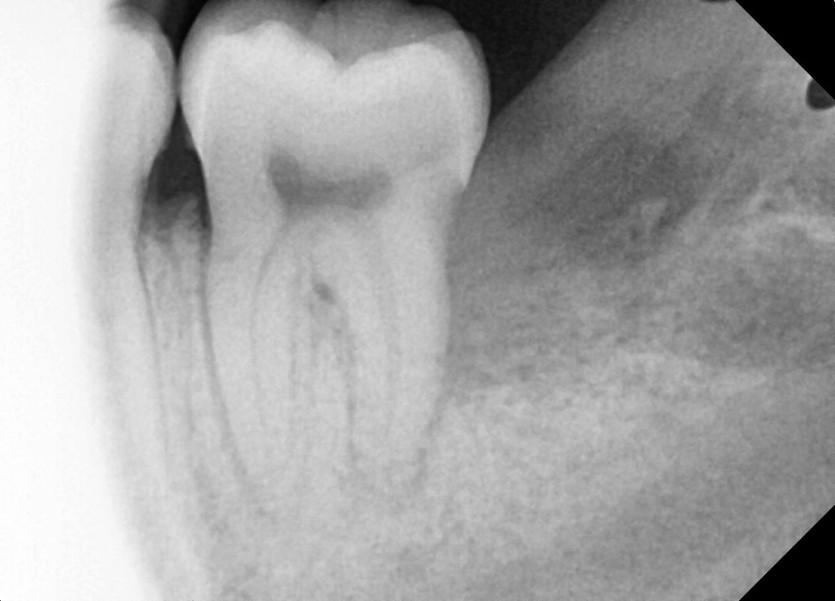

#28,38 사랑니 발치

구강 외과 전문의가 당일 발치했습니다.